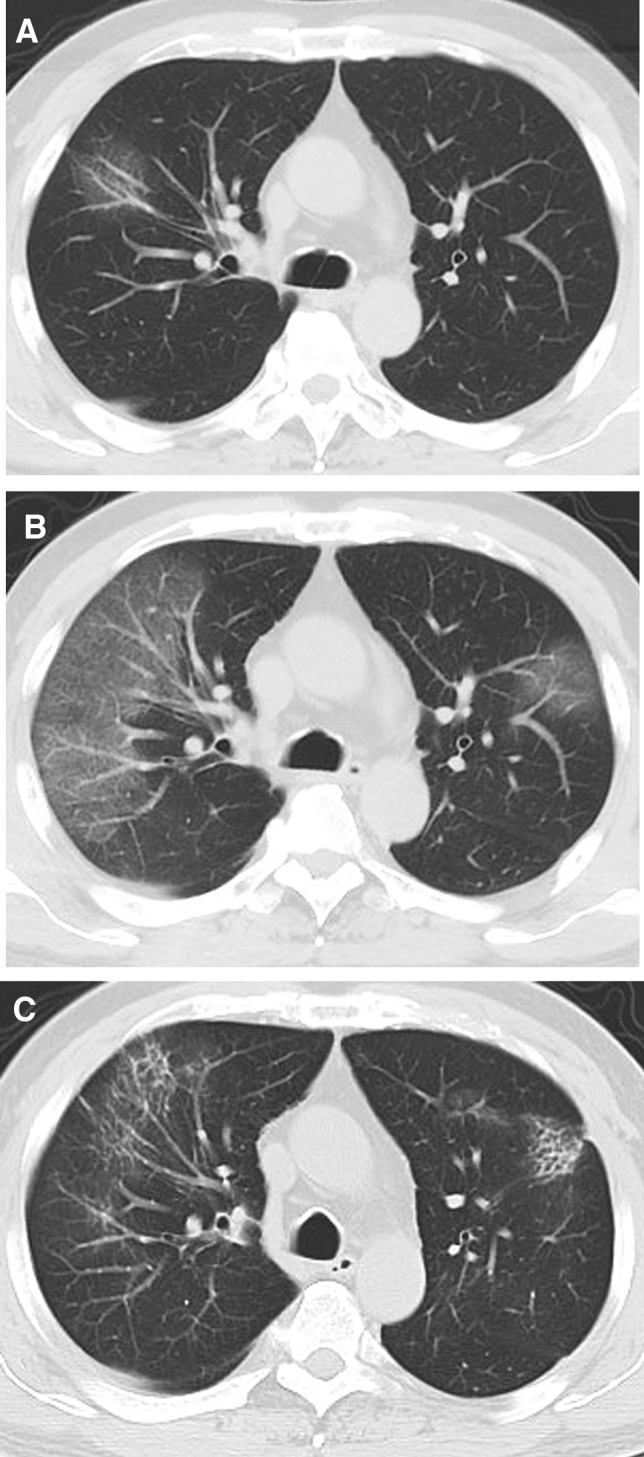

Figure 3.

CT findings of a representative COVID-19 patient in discharge group who presented with fever and fatigue, severe pneumonia, and improved in symptoms corresponding to the CT scans. (A) Scan obtained on illness day 3 shows focal ground-glass opacities in right upper lobe, with a random distribution. (B) Scan obtained on illness day 8 shows that the ground-glass opacities were increased. (C) Scan obtained on illness day 18 shows development of a residual reticular pattern.

Figure 4.

CT findings of a representative COVID-19 patient in discharge group who presented with fever and mild dyspnea, severe pneumonia, and gradually improved in symptoms corresponding to the CT scans. (A) Scan obtained on illness day 4 shows multifocal ground-glass opacities in double lower lobes, with a subpleural distribution. (B) Scan obtained on illness day 7 shows that the ground-glass opacities were increased, with superimposed interlobular and intralobular septal thickening and with diffuse distribution. (C) Scan obtained on illness day 12 shows that the ground-glass opacities were decreased, with superimposed irregular opacities. (D) Scan obtained on illness day 23 shows development of a mixed pattern.